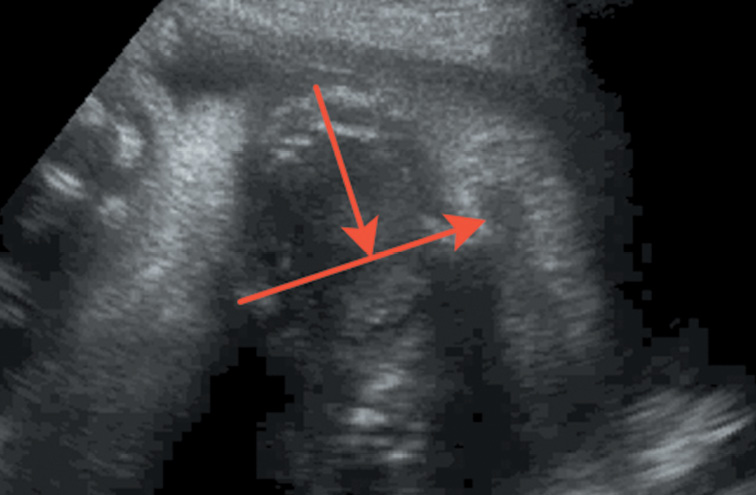

Челюстной индекс рассчитывался после измерения переднезаднего диаметра нижней челюсти плода в осевой плоскости в соотношении с бипариетальным размером (рис. 7). Данный индекс не зависел от срока гестации.

Рис. 7. Переднезадний диаметр нижней челюсти плода / Fig. 7. Anteroposterior diameter of the lower jaw of the fetus